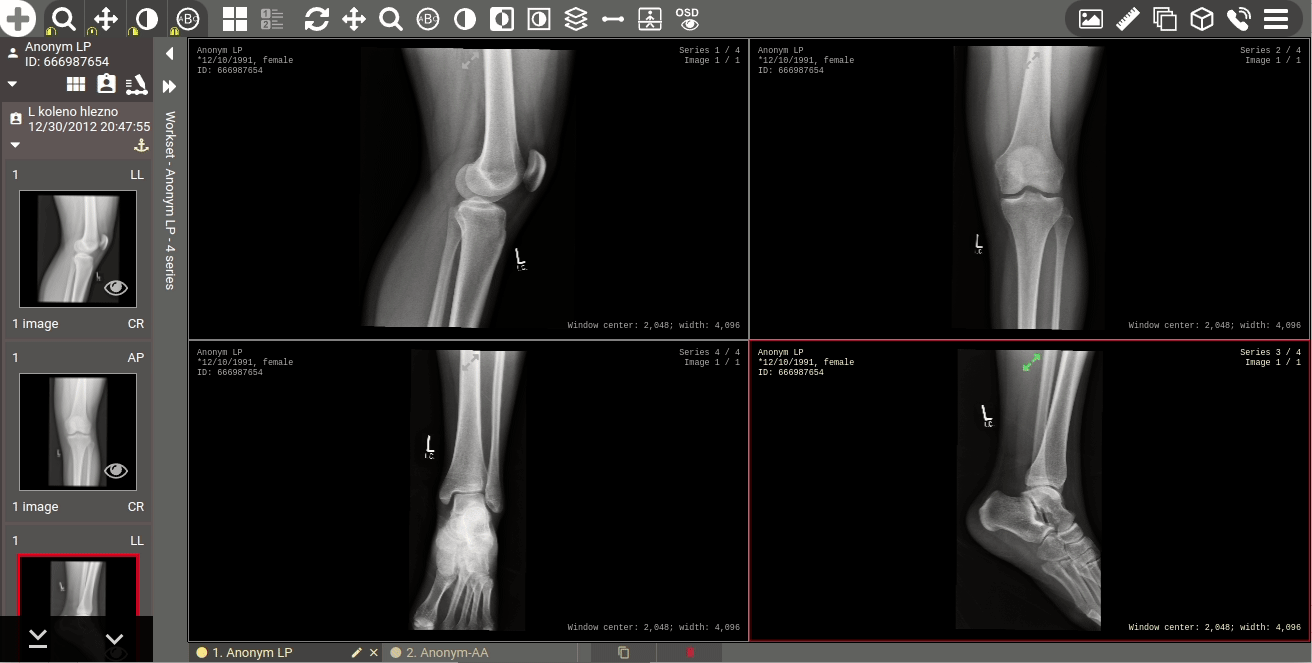

Tato nová verze přináší citelné zrychlení práce v prostředí DICOM prohlížeče, kdy došlo až ke 4násobnému urychlení načítání větších snímků do mezipaměti prohlížeče a rychlejšímu dotahování dat ze serveru do pracovní stanice. K urychlení došlo také v případě využívání Hanging protokolů, kdy došlo k jejich optimalizaci vyhodnocování a aplikování na studii a můžete tak očekávat až 10násobné urychlení zobrazení studií s aplikovaným Hanging protokolem oproti předchozí verzi a to i s rozšířením podporovaných funkcí Hanging protokolů.